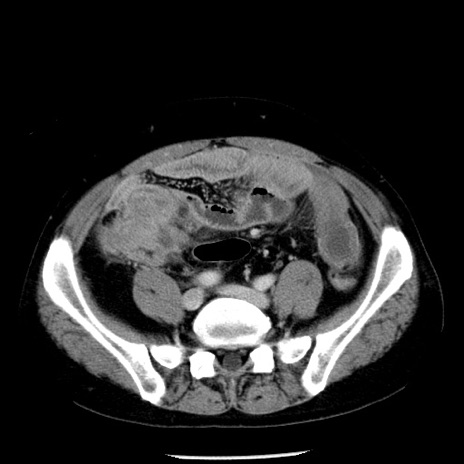

冠状断像

【症例】40歳代男性

【現病歴】2日前から胃痛あり。徐々に周期的な激痛に変化した。本日になっても激痛があるため受診。

【身体所見】意識清明、BT 38-39℃台あり、腹部:膨満、やや硬、右下腹部に圧痛あり。

【データ】WBC 8500、CRP 23.26